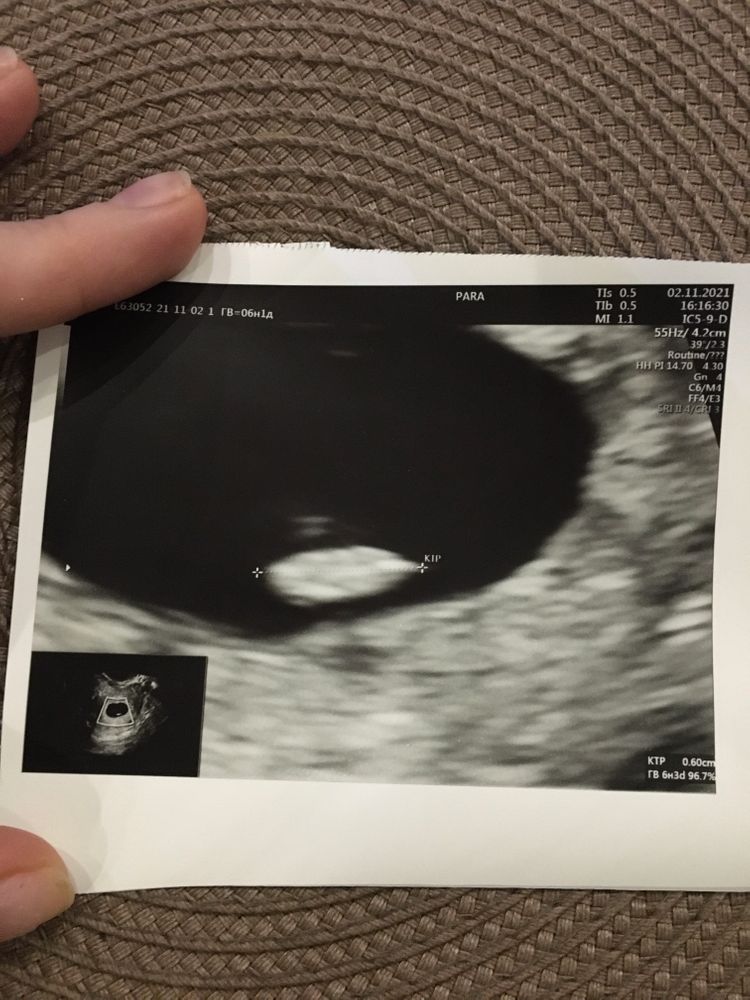

25ДПП и я беременна 😍

Какой хороший малышок ❣️😘